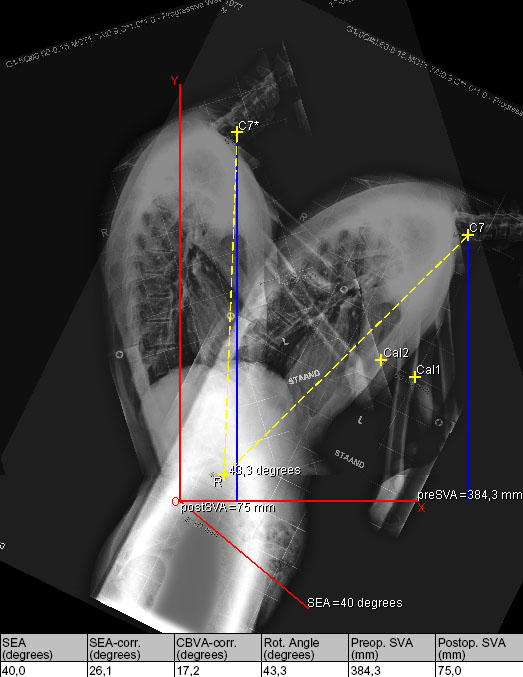

ASKyphoplan is a program for deformity planning in ankylosing spondylitis (AS). A Pedicle Subtraction Osteotomy (PSO) or closing wedge osteotomy of the lumbar spine may be considered to correct posture and spinal balance in progressive thoracolumbar kyphotic deformity caused by AS. Adequate deformity planning is essential for reliable prediction of the effect of surgical correction of the spine on the sagittal balance and view angle. The effect of a lumbar osteotomy in AS on the clinical view angle and the sagittal balance of the spine can be expressed by a mathematical equation.

ASKyphoplan is a computational program that analyses and visualises the planning procedure for sagittal plane corrective osteotomies of the lumbar spine in AS , which can be used easily in daily practice. The relationship between the planned correction angle, level of osteotomy, and sagittal balance are coupled into the program. The software can be used free of charge.